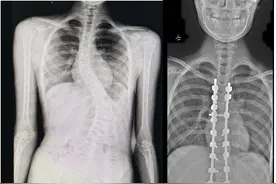

极目新闻记者 赵雪纯通讯员 荆彤 涂敏 李明静武汉一家长总觉得自己的孩子“站没站相,坐没坐相”,没想到竟是重度脊柱侧弯所致。所幸在武汉市第四医院儿童创伤与矫形中心接受脊柱矫形手术后,11岁的小姑娘终于挺直了腰杆,端正了身形。

长江日报大武汉客户端9月19日讯 以前老觉得孩子“站没站相,坐没坐相”,没想到竟是重度脊柱侧弯所致。所幸在武汉市第四医院儿童创伤与矫形中心接受脊柱矫形手术后,11岁的小姑娘珍珍终于挺直腰杆,端正了身形。